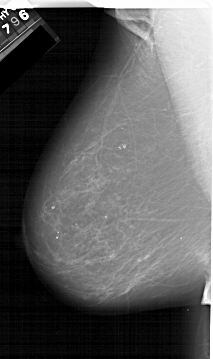

A_1597_1.LEFT_CC

LEFT_CC LINES 6091 PIXELS_PER_LINE 3706 BITS_PER_PIXEL 12 RESOLUTION 43.5 NON_OVERLAY